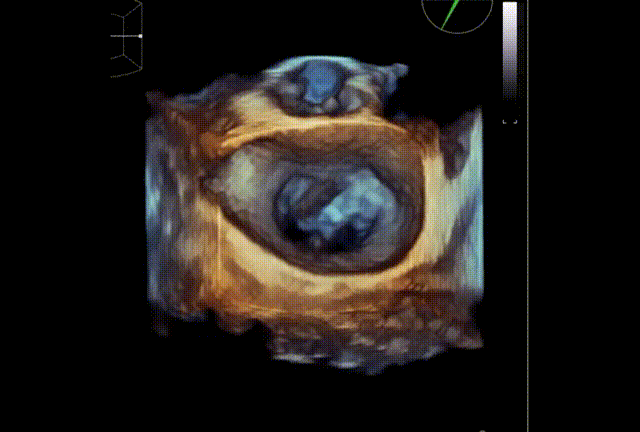

术前TEE显示重度二尖瓣反流,确认二尖瓣后瓣(P2)脱垂